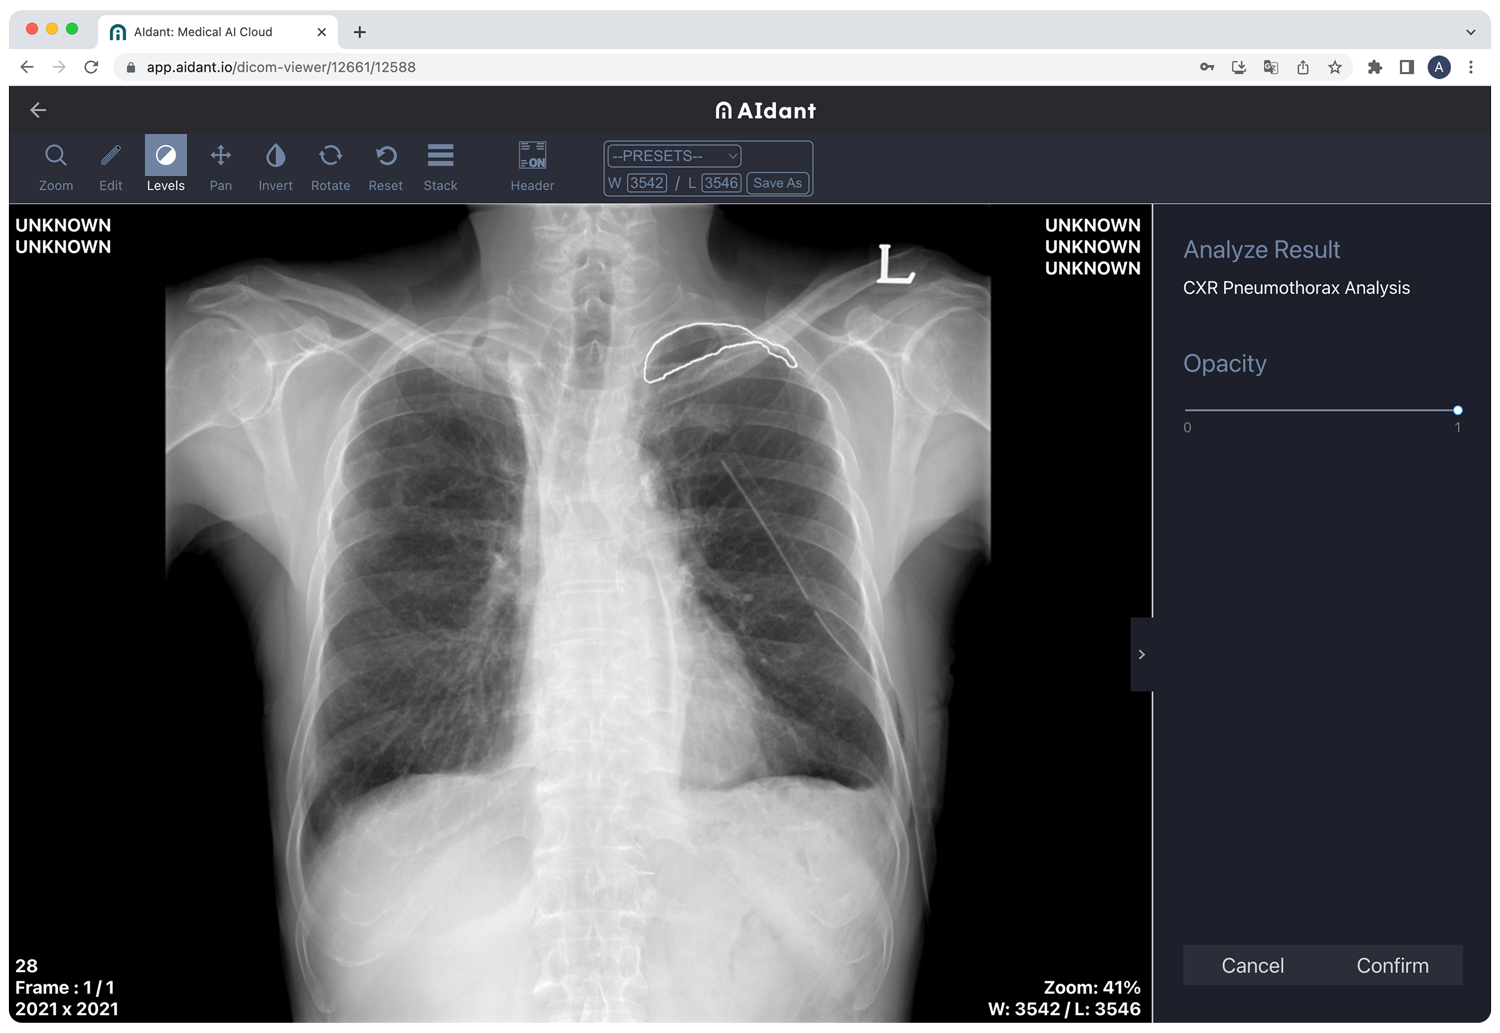

AIdant is a cloud-native medical imaging AI platform, which connects healthcare professionals (HCPs) with cutting-edge AI solutions. The company will debut its AI technology* at GITEX AFRICA 2023, the largest tech exhibition in Africa.

- Medical Image Analysis: CXR Pneumothorax, CXR Osteoporosis, CXR Infectious Disease, CXR Cardiothoracic Ratio, CXR Cobb Angle

AIdant enables HCPs to spend more time on patient care, by reducing time-consuming medical image analysis. By providing DICOM medical imaging viewer and AI analysis directly on a web browser, AIdant eliminates the need to install or invest in new equipment. HCPs can also share medical images and patient data with peers for second opinions and remote collaboration.